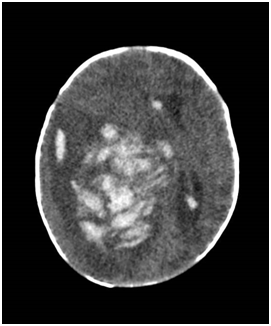

She was subsequently transferred and counselled for surgery by the paediatric neurosurgeon. Parents declined surgery in view of poor surgical outcome. The option of biopsy for definitive diagnosis and chemotherapy was discussed but declined. The parents opted for comfort care and were taught nasogastric tube insertion and basic cardiopulmonary resuscitation (CPR) before the baby was discharged against advice. On day 11 of life, the baby was admitted with vomiting and lethargy. Computerized tomography (CT) brain (Figure 4) showed marked increase in the midline shift and baby passed away the same night, with intracranial tumour contributed by tumour haemorrhage confirmed as the cause of death. No post-mortem was performed.

Figure 4 CT of baby brain showing a heterogenous enhancing mass that is occupying right cerebral hemisphere, measuring 8.0 x 5.3 x 7.1 cm, causing significant midline shift towards the left. There were areas of hyperdensity showing intraventricular extension of haemorrhage to the right frontal horn, posterior horn and third ventricle.